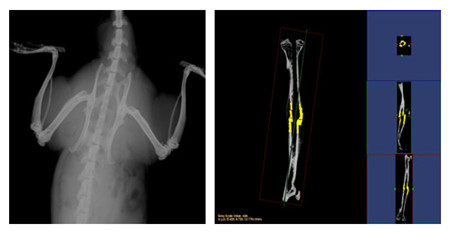

小动物CT服务通过采用锥形X线束,不仅能够获得真正各向同性的容积图像,提高空间分辨率,提高射线

利用率,而且在采集相同3D图像时速度远远快于扇形束CT。可以对不脱钙骨骼和动物牙齿进行microCT检测

服务,分析其内部结构和提供给您高清晰、高质量的扫描图像。活体研究对象通常为小鼠、大鼠或兔等活体小

动物,可以实现生理代谢功能的纵向研究,显著减少动物试验所需的动物数量;离体研究对象通常为离体标

本(例如骨骼、牙齿)或各种材质的样品,可分析其内部结构和力学特性。

结果示意图: